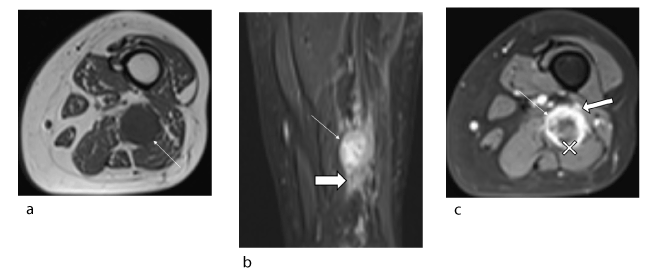

Figure 1. Female patient, 43 years old: schwannoma of the sciatic nerve at the right sciatic notch. (a) Axial T1 slice (TR/TE 850/11) showing a neurogenic lesion (arrow) with isosignal, well-defined margins and no spread to adjacent soft tissues (solid arrow) (b) Fluid-sensitive coronal slice (TR/TE 2200/34) showing the hyperintense lesion (arrow) and absence of target sign. The tumour is off-centred relative to the sciatic nerve (arrowhead). (c) Axial T1-weighted fat-suppressed post-gadolinium slice showing heterogeneous uptake in the tumour (arrow)